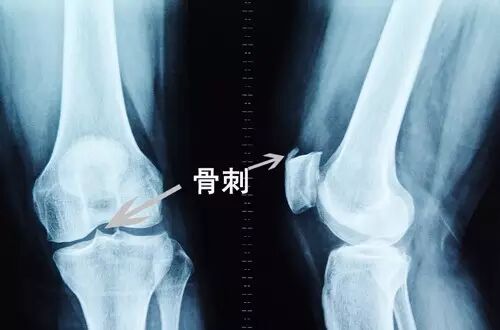

① X线片:关节的X线片可记录病变在大体方面的异常,反映关节损伤程度、病变进展范围及对治疗的反应,其是骨关节炎患者的常规检查项目;